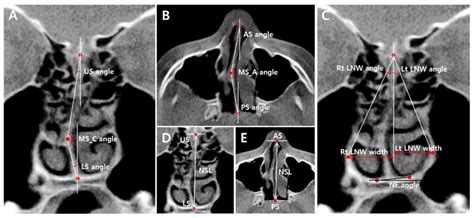

Anatomical representation of the nasal cavity

To confirm the presence of a nasal bone spur, an otolaryngologist (ENT specialist) will perform a physical examination. They will typically use a nasal endoscope—a thin, flexible tube with a light and camera—to get a high-definition view of your nasal architecture. In some cases, a CT scan may be ordered to visualize the bony anatomy in three dimensions, which is particularly helpful if surgical intervention is being considered.